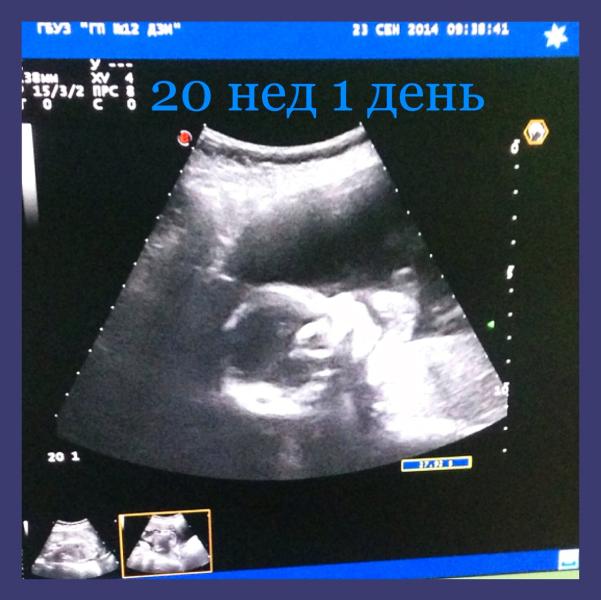

А у нас будет мальчик!) 🎉🎉🎉💕

И весим мы уже 340 грамм) 😘😘😘